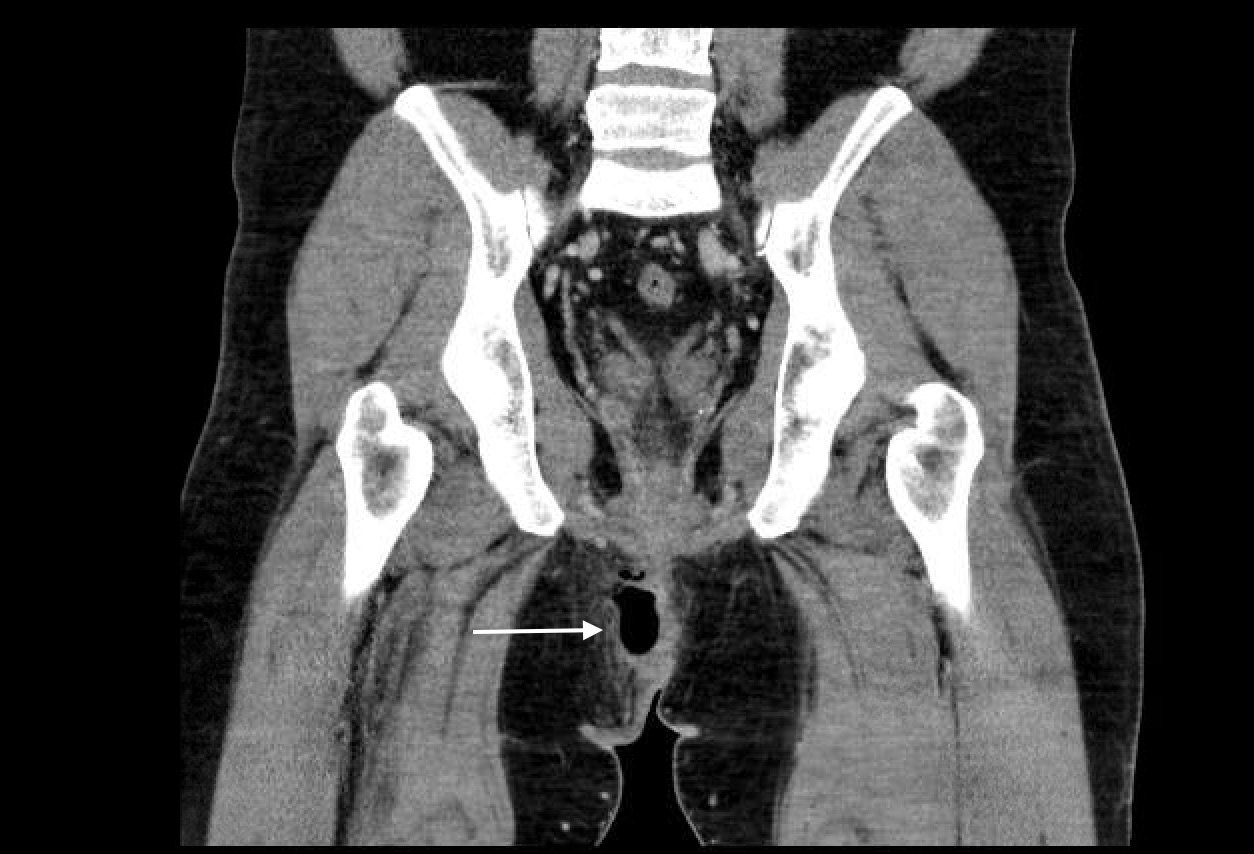

Computed tomography (CT) of the Pelvis with intravenous (IV) contrast revealed a 5.7 cm x 2.4 cm air-fluid collection in the right perianal soft tissue along the right gluteal cleft, with surrounding fat stranding, consistent with a perianal abscess with cellulitis.

A pelvic CT with IV contrast can be used to differentiate between a perianal abscess, which is located beneath the skin of the anal canal and does not transverse the external sphincter, and a perirectal abscess, which is located beyond the external anal sphincter. Ultrasound is emerging as a possible alternative imaging modality; however magnetic resonance imaging (MRI) and CT scans remain the modalities of choice. 3, 4, 5, 6